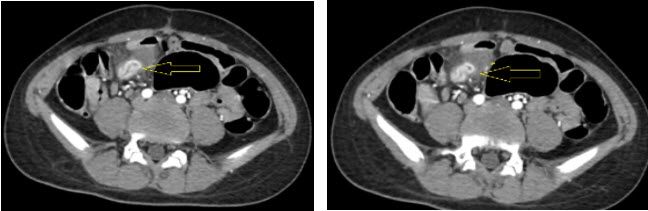

Bệnh nhân được truyền 2 đơn vị hồng cầu khối đồng thời nội soi dạ dày tá tràng và đại tràng để tìm nguyên nhân chảy máu. Kết quả nội soi dạ dày: Viêm xung huyết thân vị. Nội soi đại tràng: lòng đại tràng nhiều máu đỏ sẫm, không phát hiện nguyên nhân gây chảy máu, thấy máu qua van hồi manh tràng. Nhận định đây là một trường hợp xuất huyết tiêu hóa nguyên nhân từ ruột non.Chỉ định chụp CT mạch máu. Kết quả: Vùng hố chậu phải, cạnh hồi tràng có khối cấu trúc hình túi kích thước khoảng 1,5 x 4,5cm, niêm mạcngấm thuốc sớm, mạnh, không đồng nhất, đào thải ở thì tĩnh mạch, không thấy thoát thuốc vào ống tiêu hoá (Hình 1). Kết luận: khối cấu trúc hình túi, cạnh hồi tràng, ngấm thuốc bất thường ở niêm mạc.

Hình ảnh CT scan ổ bụng

Hình 1. Hình ảnh CT scan ổ bụng

CT scan ổ bụng: chỉ ra ổ đọng thuốc ở thì muộn, cấu trúc tù chứa dịch và hơi liên tục với ruột non trong trường hợp chảy máu do túi thừa Meckel[5]. CT thường quy được cho là ít có giá trị trong chẩn đoán túi thừa Meckel ví khó lòng phân biệt túi thừa với quai ruột bình thường [1]

Với phương tiện hiện có chúng tôi đã chọn chụp CT scan mạch máu. Trên phim dựng hình mạch máu không thấy di dạng mạch máu ruột, không thấy động mạch viteline. Tuy nhiên trên CT scan chúng tôi thấy niêm mạc ruột ở vị trí hồi tràng ngấm thuốc cản quang mạnh đồng thời tại vị trí này có 1 cấu trúc cụt chứa hơi thông với đoạn hồi tràng đó. Khả năng bệnh nhân có túi thừa Meckel, niêm mạc túi thừa và đoạn hồi tràng lân cận ngấm thuốc mạnh khả năng sung huyết.